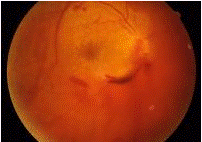

Một số bệnh nhân có thể có cảm giác có chớp sáng trước mắt, thường gặp trong trường hợp xuất huyết dịch kính có kèm theo các rách của võng mạc.Thăm khám lâm sàng cho thấy, bên cạnh các triệu chứng của chấn thương xuyên và chấn thương đụng dập nói chung (sẹo giác mạc, sẹo củng mạc, đục vỡ thuỷ tinh thể, lệch thuỷ tinh thể, máu tiền phòng…), có thể thấy sự xuất hiện của máu trong buồng dịch kính. Tuỳ theo mức độ máu trong buồng dịch kính, chúng ta có thể thấy máu trong buồng dịch kính có thể chỉ là một dải hoặc từng đám trôi nổi trong buồng dịch kính hay toàn bộ buồng dịch kính là máu. Trong trường hợp còn có thể quan sát được đáy mắt, có thể thấy một số tổn thương phối hợp của hắc võng mạc như xuất huyết hắc-võng mạc, rạn màng Bruch, rách võng mạc…